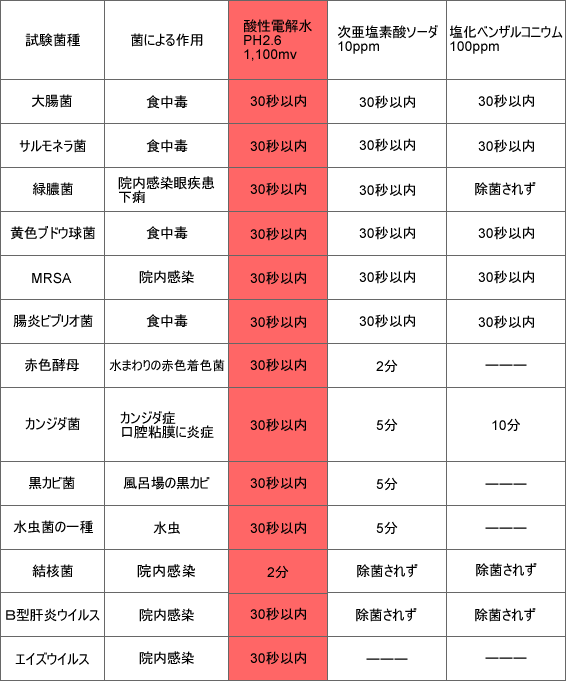

当院で新たに導入した強電解水の除菌力データ

【強電解水】

【強電解水】

当院では新たに水道水に塩化ナトリウムを加え特殊な電気分解を

行うことで洗浄・除菌にご利用できる強電解水を生成する装置を

導入しました。強電解水でレジオネラ菌。O-157、エイズ菌、

新型インフルエンザなど多くの有害微生物を死滅させることが出来ます。

しかも薬品ではなく、数分後にはお口の中で元の水に戻ってくれますので、

アレルギーが起こりにくく副作用が起こりません。また、化学薬剤のように薬剤耐性・

残留性がなく、人体に無害です。地球にも人体にも害がない安全性の高い水です。

歯科だけでなく皮膚科を含めて多くの施設で利用されています。

むし歯や歯周病の原因はプラーク(歯垢)中の細菌ですが、強電解水により

原因菌は瞬時に殺菌されます。強電解水で含嗽(ぶくぶくうがい)する

ことにより、口の中の細菌を殺菌するだけでなく、歯面に着くプラーク

(歯垢)の形成をも抑制することによって、むし歯や歯周病を予防します。

含嗽(ぶくぶくうがい)を、一回だけでなく2~3回繰り返すことで、

より有効になります。